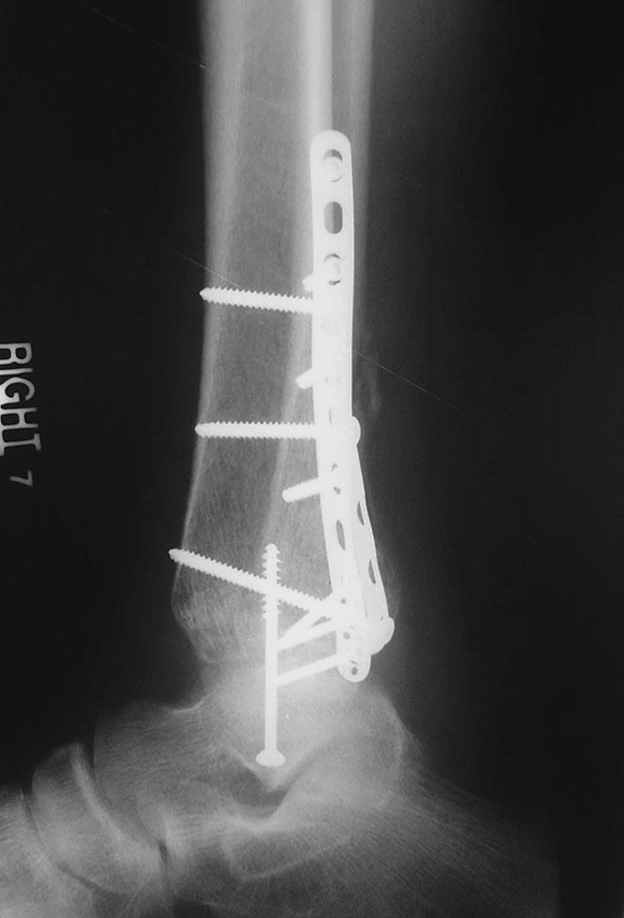

Второй случай сделан из одного разреза

Дж

ЕЧ LISS plate, mininvasive approach - luxurous !

Вопрос практического характера - такой подход рутинный или при определенных показаниях и каких? Спрашиваю потому, что при потоке больных - закрытая голень, бедро, голеностоп и т.д. лучевая нагрузка должна быть немалая, каковы показатели дозиметра после такого операционного дня и при 2-3 операционных днях в неделю по 5-6 случаев (не считая ургентностей)?

С точки зрения : Сгорая сам - свети другим :-)) это вполне понятно, но личная практика показывает, что далеко не все пациенты относятся волнительно и критично к длине кожного разреза. Подозреваю, что это и есть критерий при выборе техники фиксации?

На прямой проекции послеоперационного Рг макроскопически все выглядит очень анатомично, при микроскопическом ( :-)) ) рассмотрении можно все-таки заметить вальгизацию тарана, суставная щель в латеральном отделе сустава несколько уже , чем в медиальном при отсутствии латерального смещения тарана. У меня был аналогичный случай (без LISS , без мини доступа) с вальгусным наклоном тарана при восстановленном ankle mortise при последовательном наблюдении с интервалами в 6-8 недель в послеоперационном периоде отмечалось прогрессирующее сужение суставной щели в латеральном отделе сустава, закончившееся посттравматическим ОА, к счастью боли умеренные, купируемые аналгетиками или своими эндорфинами:-))(активная пациентка, у которой нет времени на болезни....) Какова жизненная ситуация в приведенном вами случае? И последнее, что я хотел бы прояснить для себя - фиксация внутренней лодыжки: я обычно комбинирую фиксацию компрессирующим винтом со спицей - по идее ротационная стабильность должна быть лучше, чем один винт, каковы ваши наблюдения в этом плане?